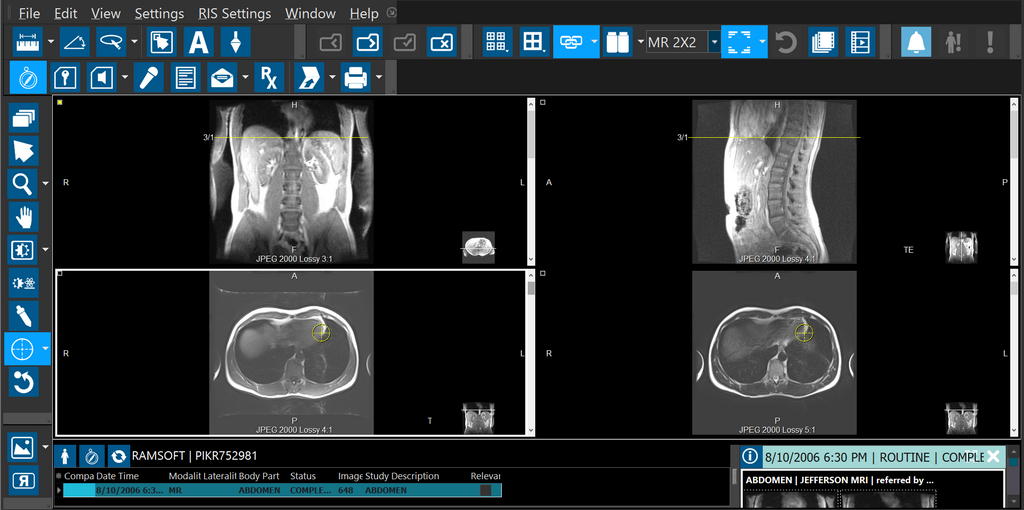

The Cross-hair Pointer is an interactive tool designed to visualize suspected pathology in every series. The RamSoft Cross-hair Pointer icon is unique as it shows every plane and technique available that contains the selected point. The tool is activated from the Image Tools toolbar. The following screenshots illustrate the application of the RamSoft Cross-hair Pointer.

Note: This tool is visible from the Study Desktop toolbar only when you are viewing MR/CT/PT images.

The option Display All Matching FrameSets is part of the Cross-hair Pointer tool drop-down menu. With this option on, clicking and releasing the Cross-hair Pointer at a location on the image causes the viewing protocol to display all Framesets containing the point; every viewport displays the 3D point location based on the matched series. Linking is ignored.

Selecting Restore Viewport Layout option from the drop-down menu restores the original viewing protocol.